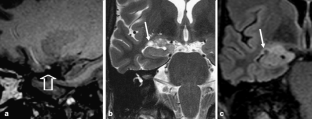

From a total of 61 DNTs, 48 simple and 13 complex variants were identified. Multiple or single pseudocysts in a cortical/subcortical location with small cysts sometimes separated from the tumor represented the glioneuronal element and were found in all DNTs. FLAIR hyperintense tissue was found between pseudocysts but—in neocortical DNTs—also circumscript in deeper tumor parts. Calcification and hemorrhages in this location occurred in four of 13 complex variants, and one of these patients was also the only one with tumor growth. Patients with complex variants had earlier seizure onset, and complex variants were more often located outside the temporal lobe. Although complex variants represented a higher diagnostic challenge, misdiagnoses also occurred in simple variants. One of five of DNTs showed contrast enhancement, which varied on follow-up studies with enhancing parts becoming nonenhancing and vice versa.